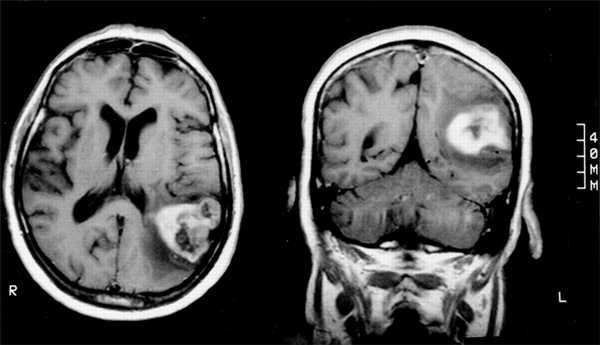

Любой пациент с симптомами и признаками синдрома Герстманна должен быть оценен с помощью нейровизуализации МРТ / КТ. Аномалии должны быть видны на доминирующей угловой извилине с вовлечением или без окружающих областей. Выявленные аномалии должны отличаться в зависимости от причины.

- Церебральная МРТ. Более информативна в диагностике ишемических нарушений, дегенеративных процессов угловой извилины. Позволяет оценить распространенность процесса. Рассеянный склероз характеризуется наличием бляшек на МРТ изображениях, лейкоэнцефалопатия — аномальных гиперинтенсивных очагов на Т2-взвешенных изображениях.

На фото область мозга, которая страдает при синдроме Герстманна Штреусслера Шейнкера

Помимо генетических исследований и тестирования пациента, его обследуют при помощи магнитно-резонансной томографии головного мозга - она помогает выявить очаг поражения на всех стадиях развития синдрома, определить изменения в коре и структуре серого вещества, выявить ущемление нервных волокон и проблемы с кровотоком.

- МРТ головного мозга (для выявления пораженных очагов на любой стадии заболевания, изменений в области коры или полушарий мозга, ущемленных нервов или сосудов).